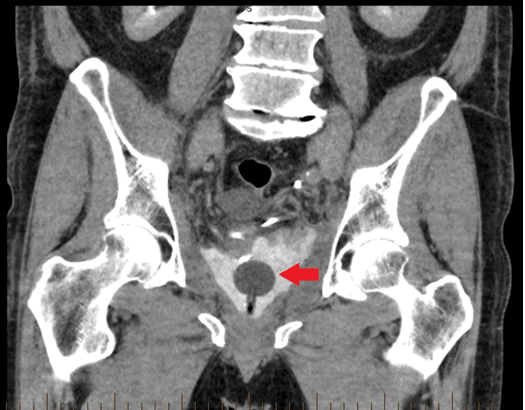

A 68-year-old was male presented to the hospital on day-8 post robot-assisted laparoscopic radical prostatectomy (RALRP) for routine catheter removal and trial of void. He had no other significant medical history and the procedure was performed for Gleason 7 biopsy-proven prostate adenocarcinoma. On admission, he reported feeling unwell for the last two days and passing dark blood-stained urine with debris, but no symptoms of infection were experienced. These symptoms were preceded by an episode of "coughing fits". On examination, the patient was afebrile and his vital signs were within normal range. Cardiopulmonary examination was normal and abdomen was soft and non-tender. The laparoscopic surgical wounds appeared clean and healthy. Pelvic computed tomography scan showed disruption of the anastomosis with the catheter lying within the contrast-filled prostatic cavity (Figure 1).

Figure 1: Pelvic computed tomography scan showing disruption of the anastomosis with the catheter lying within the contrast-filled prostatic cavity.